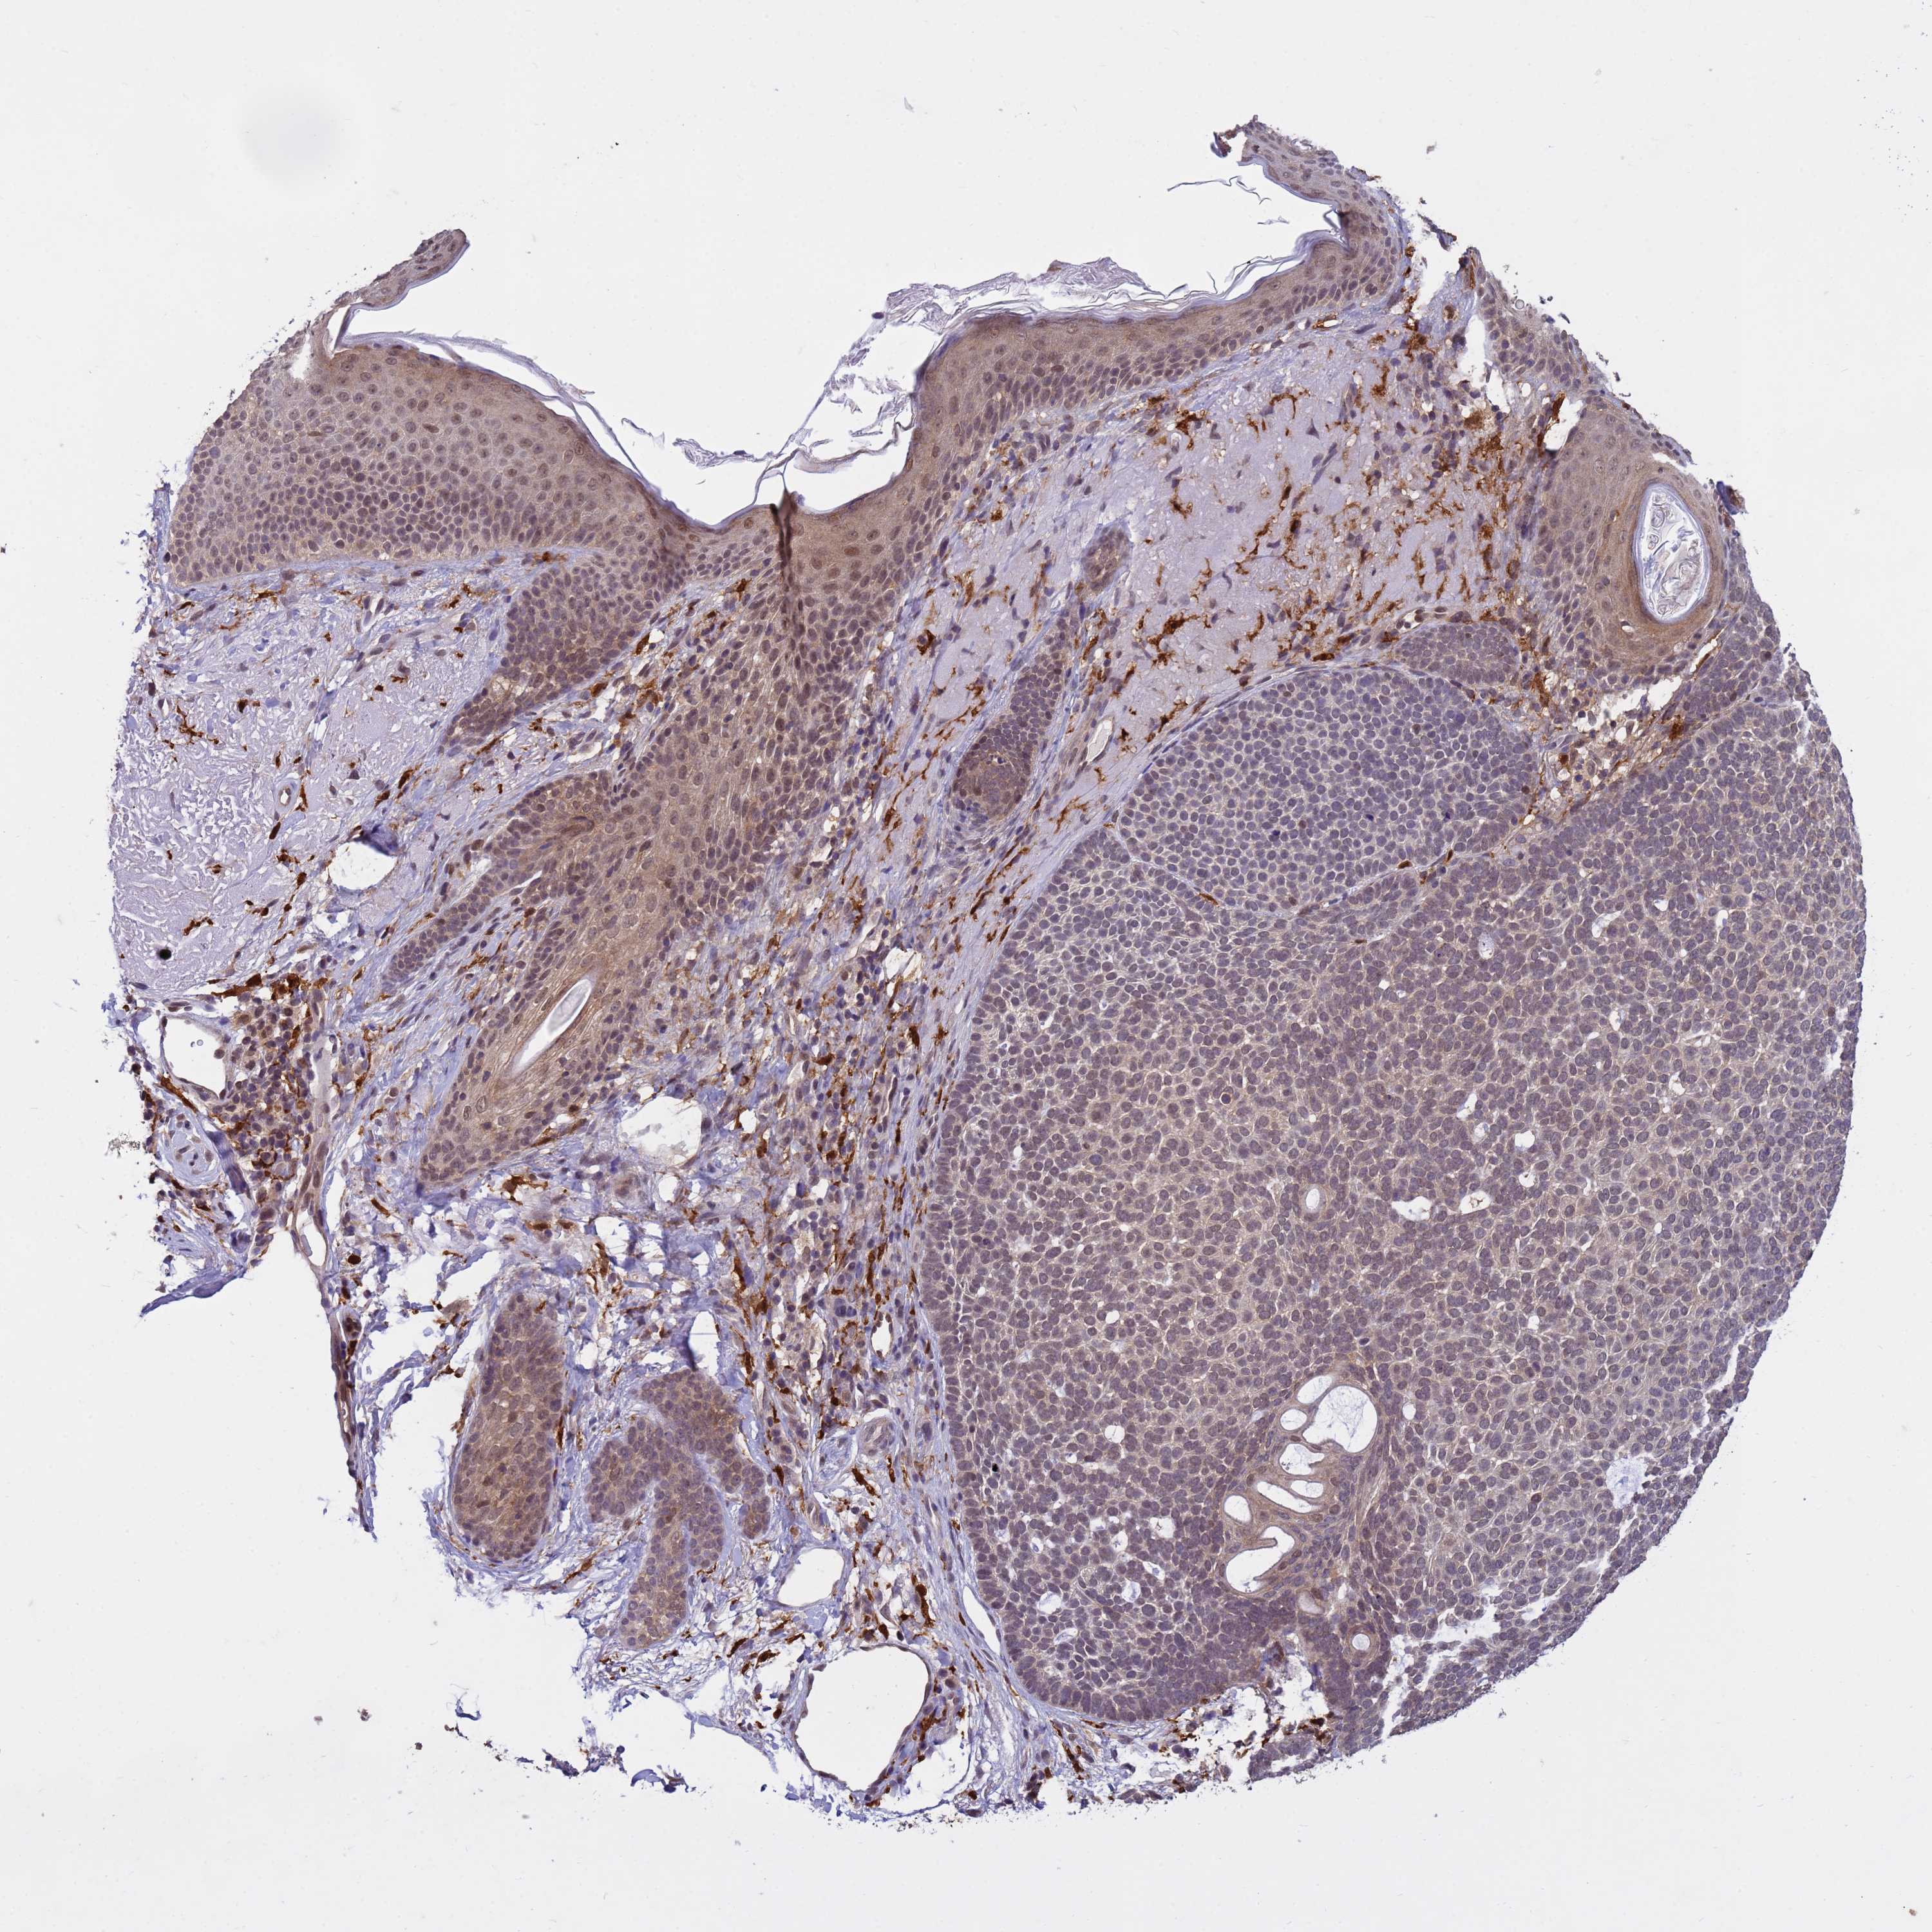

SKIN CANCER - Protein expressioni

A mouse-over function shows sample information and annotation data. Click on an image to view it in a full screen mode. Samples can be filtered based on level of antibody staining by selecting one or several of the following categories: high, medium, low and not detected. The assay and annotation is described here.

Each image is clickable and will lead to virtual microscopy that enables deeper exploration of all samples and also displays staining intensity scores, fraction scores and subcellular localization as well as patient and tissue information for each sample.

Antibody HPA045649

Staining

High

Intensity

Strong

Quantity

>75%

Location

Nuclear

Squamous cell carcinoma, NOS